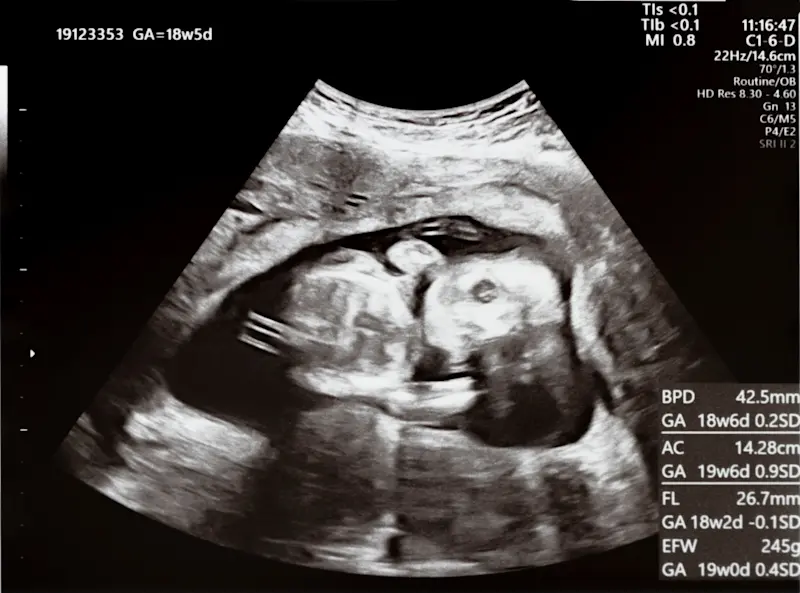

1-2. 超音波(エコー)検査による初産 予定日の修正

より正確な予定日を知るために、妊娠初期に行われる超音波(エコー)検査が非常に重要になります。

特に妊娠6~11週頃に行われる、胎児の頭殿長(CRL:頭からお尻までの長さ)を測定する検査は、その後の予定日確定において最も重要です。

この時期の胎児のサイズには個人差が少なく、精度が高いため、多くの産科施設ではこのCRLに基づいて算出された予定日を、最終的な予定日として確定します。

妊娠中期以降の測定値は、胎児の成長に個人差が出るため、予定日確定には使われないことが多いです。